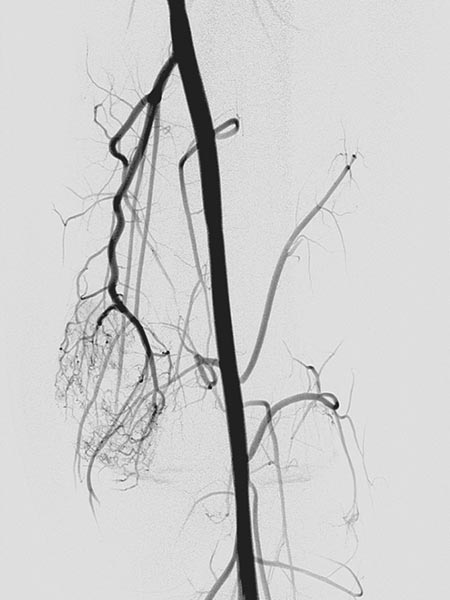

Super-selective catheterization of the feeding artery with a microcatheter again depicts multiple, fine arteriovenous fistulas, but not the immediate venous outflow as would be typical of an AVM. However, the visible arteriovenous fistulas are unusually prominent in this venous malformation.

The microcatheter is now used to selectively embolize the fistulas with ethylene-vinyl alcohol copolymer, which as a liquid agent is distributed throughout the fine fistulae.

The radiographic overview after embolization of the AV fistulas shows the selective cast specimen of the radiopaque embolic agent filling the fistulas.

In the final overview digital subtraction angiography after embolization, the fistulas are completely occluded.